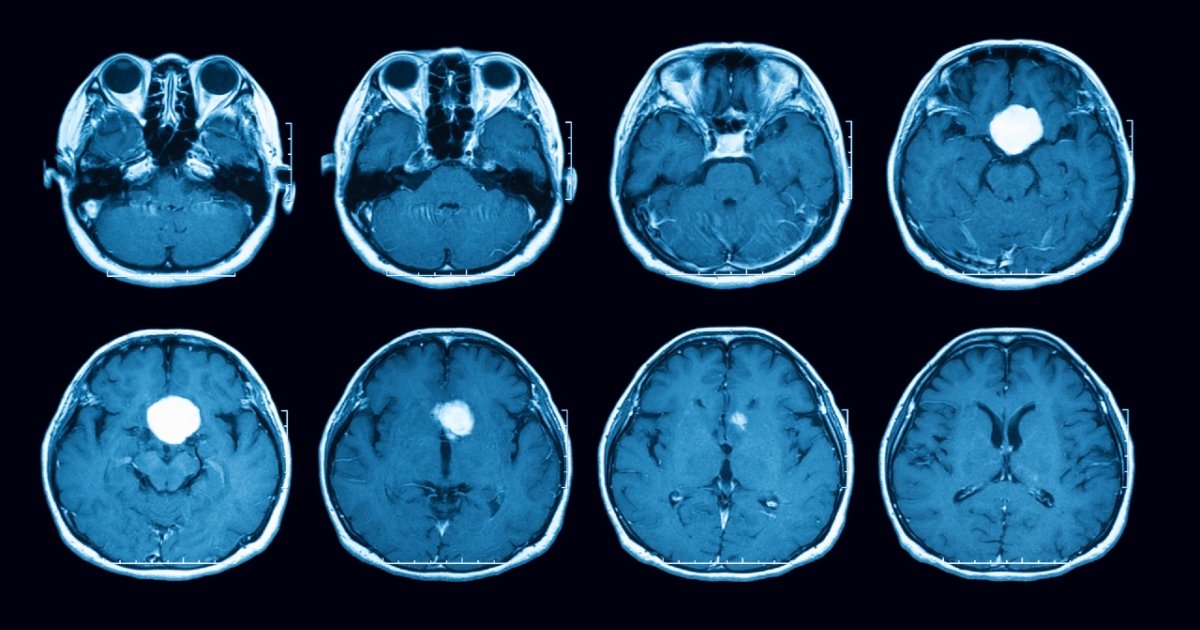

imagem que mostra tumores da hipófiseDiagnóstico e tratamento

O diagnóstico de prolactinoma é realizado por meio de exames de sangue para verificar os níveis de prolactina, além de exames de imagem, como ressonância magnética, para identificar a presença e o tamanho do tumor.